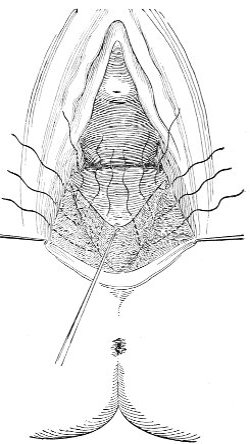

Slight Median laceration of the Perineum.—In this injury the tear takes place through the fourchette. Posteriorly it may extend as far as the sphincter ani muscle. Upward it may extend for an inch up the posterior vaginal wall. The appearance of this tear is shown in Fig. 33. It will be noted that, as this tear takes place in the median line, none of the muscles that support the perineum are involved, nor are the planes of fascia injured. The perineum is slightly split, and the insertions and origins of the muscles and the fascia are slightly separated. The supporting structures of the perineum and the pelvic floor are, however, uninjured.

Fig. 33.—Recent slight median laceration of the perineum: sutures introduced.

If this tear is detected after labor, it should be closed by the immediate operation. A slight tear involving chiefly the cutaneous aspect of the perineum should be closed by three or four sutures introduced from the outside, as in Fig. 33. The needle should be introduced about a quarter of an inch from the edge of the wound. It should not be passed parallel with the plane of the lacerated surface, but should be swept outward and then inward toward the 68 angle at the bottom of the tear (Fig. 34). It may either emerge at the angle and be re-introduced, or it may be passed directly through to the skin-margin on the opposite side of the wound. If the suture is passed in this way, there will be perfect apposition throughout the whole surface of laceration. If the sutures are improperly passed, there may result only apposition of the skin-edges.

Fig. 34.—Diagram representing the correct and the incorrect method of passing the suture for closure of slight perineal laceration.

If the laceration extends up the posterior vaginal wall, two sets of sutures must be introduced—one on the vaginal aspect of the tear, and one on the skin aspect (Fig. 35).